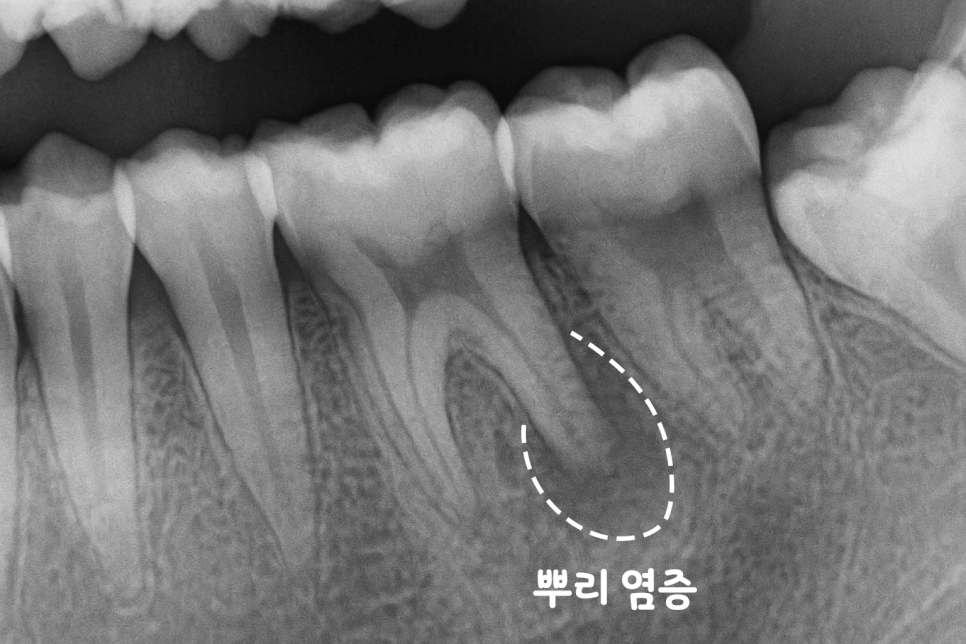

또한 뼈 속에 숨어있는 염증이나,

뿌리 끝부분의 감염도

엑스레이를 통해서만 확인이 가능합니다.

이런 병변들은 증상이 나타나기 전까지는

환자분도 모르는 경우가 대부분입니다.